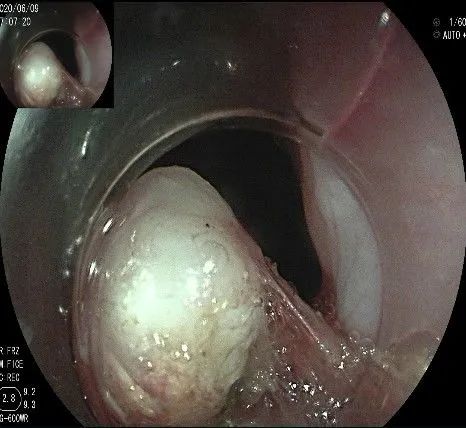

沿切开的边缘,从口侧开始向下进行粘膜下剥离,剥离的间隙是瘤体之上粘膜之下,期间反复进行粘膜下注射。

随着剥离的进行,瘤体与周围组织的关系越来越清晰。

此时瘤体基底部已暴露出来,起源于固有肌层。

这是最后的“根”部。

换用IT刀可以轻松剥离,又避免切入过深造成穿孔。

剥离接近完成,最后连接的薄层组织。